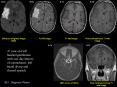

A single shot EPI sequence can freeze the macroscopic pulsating ... FLAIR image showing bifrontal gliosis and encephalomalacia. Head trauma:Hypo-perfusion ... – PowerPoint PPT presentation